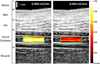

Methods: A syringe pump was used to push a solution of gas-filled microbubbles at specific flow rates through a shunt catheter while a high-frequency ultrasound imaging system was used to collect ultrasound images for offline processing. Displacement maps and velocity profiles were generated using a speckle-tracking method based on a cross-correlation algorithm. An additional correction factor, to account for a predictable underestimation and to adjust the measured flow rates, was calculated based on the geometry of the ultrasound imaging plane and assuming a simple model of laminar flow.

Results: The developed method was able to differentiate between physiologically relevant flow rates, including no flow and 0.006 to 0.09 ml/min, with reasonable certainty. The quantitative measurement of flow rates through the catheter using this method was determined to be in good agreement with the expected flow rate.